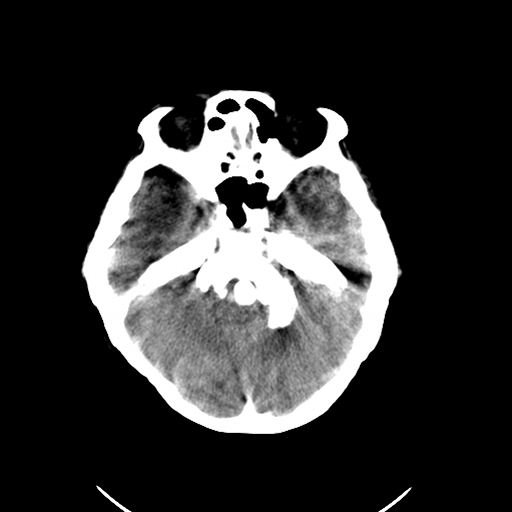

标题: CL0976:颅骨凹陷征 [打印本页]

标题: CL0976:颅骨凹陷征

女,56岁,头痛,没有其他的神经系统的阳性体征

颅底陷入是枕大孔周围骨,包括枕骨基底部、髁部和鳞部上升向颅腔内陷入的畸形。环、枢椎也随之上升、突入。多属枕骨及环枢椎先天性发育异常,也可继发于引起颅底软化的疾病、成骨不全或佝偻病等。

颅底凹陷症!这样横断位未见过,平时都是颈椎侧片所示。建议颈椎mr检查。

颅底凹陷.典型.